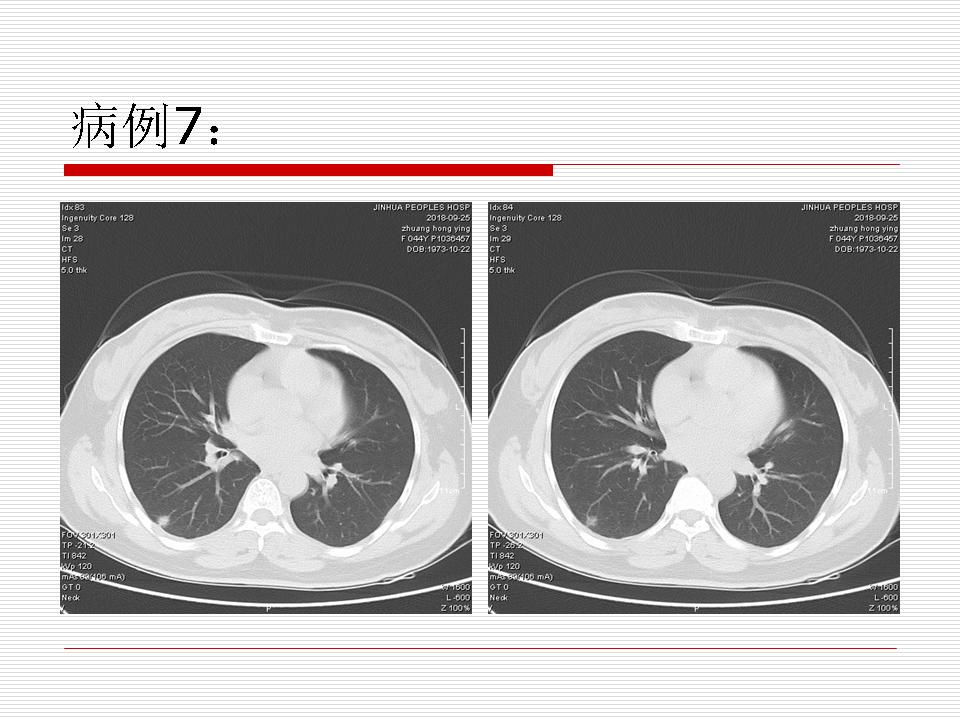

肺部阴影永恒且最重需要鉴别的是:到底是炎症还是肿瘤?但临床的病例中的影像表现难以界定或有些肿瘤特征,同时又有些炎症特点是非常常见的情况。作为临床医生我们怎么去总结分析,并找到之所以是炎症或之所以是肿瘤的细微差别或特点非常重要,也非常有用。2019.12.7浙江省2019年胸心外科学学术年会在宁波召开时,我的临床病例分析与经验总结<那些像肺癌的炎症与像炎症的肺癌>获得在大会交流的机会,以下为该PPT的内容,与你分享,希望对同道有益,有借鉴与启迪。若有探讨与进一不完善的建议,欢迎文末留言讨论: